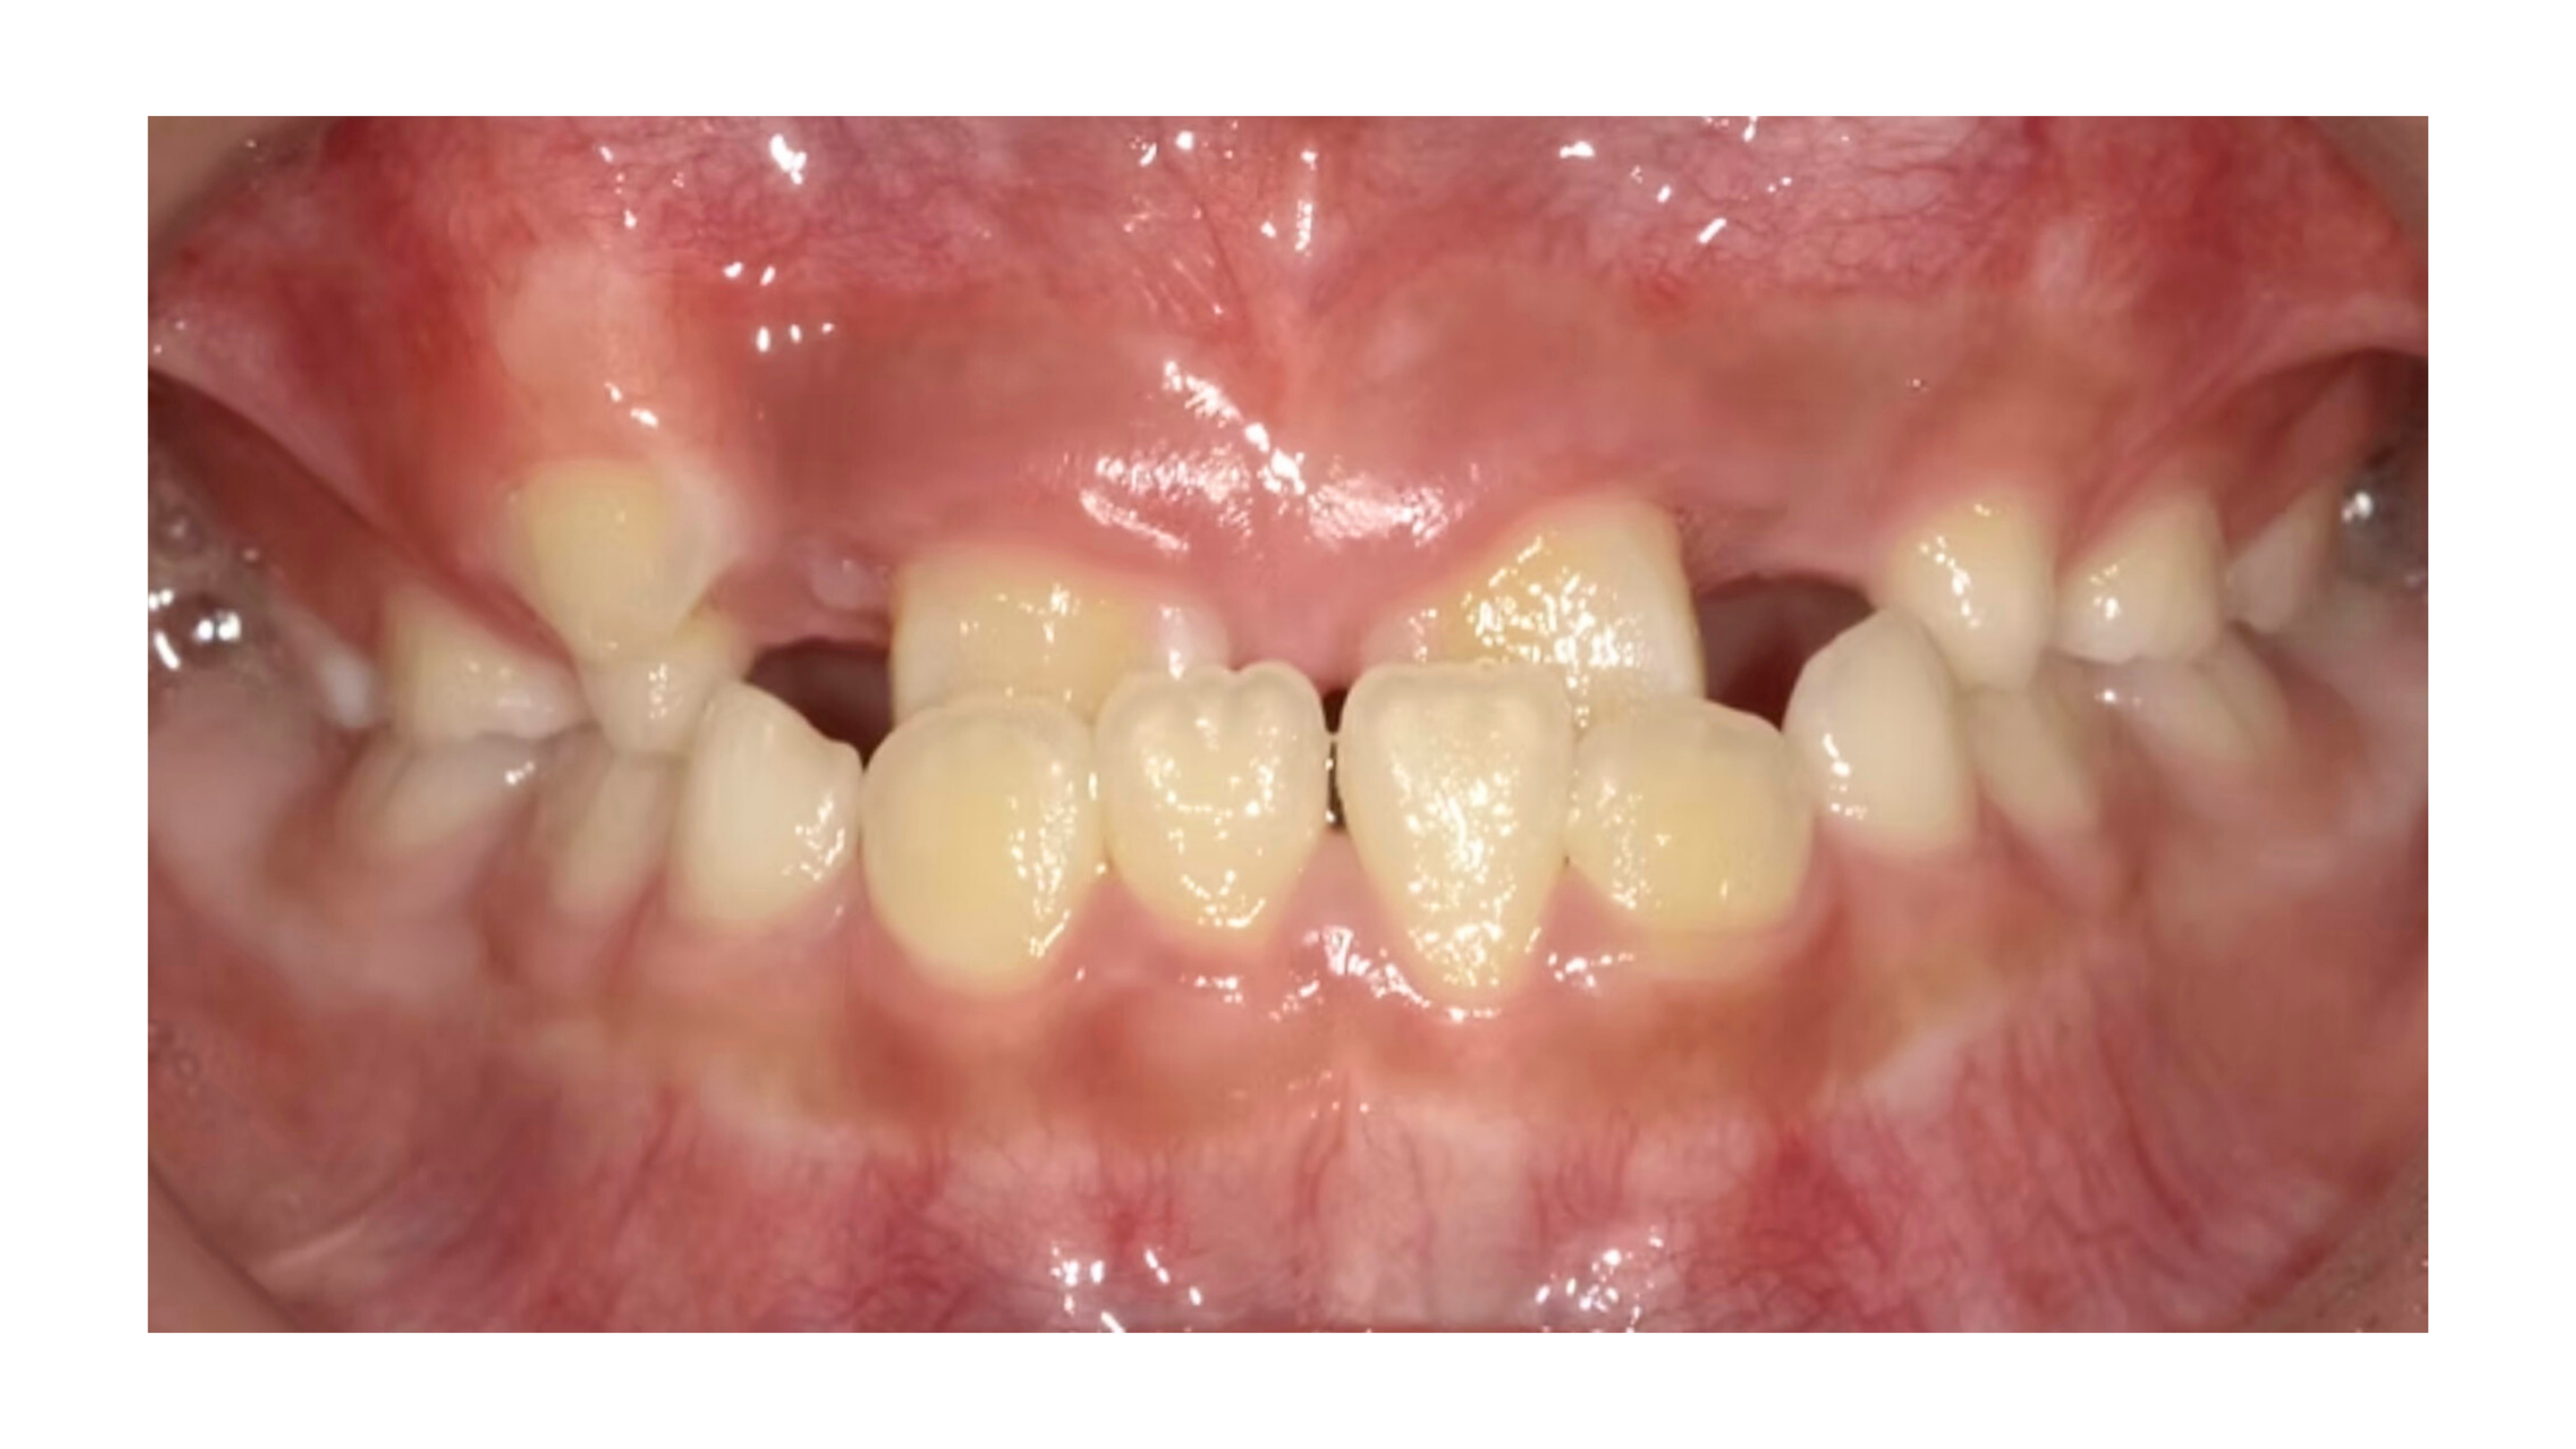

今回は反対咬合(受け口)でご相談いただいた症例をご紹介します

〈7歳の男の子〉

お母さまから「噛み合わせが逆になっているのが気になる」とご相談をいただきました。

診てみると、

• 重度の反対咬合(受け口)

• 上の前歯部分に2本の過剰歯が存在

• 上アゴの成長不足

といった状態があり、このまま成長すると「永久歯が生えるスペースが足りず、さらに歯並びが悪化する」ことが予想されました。